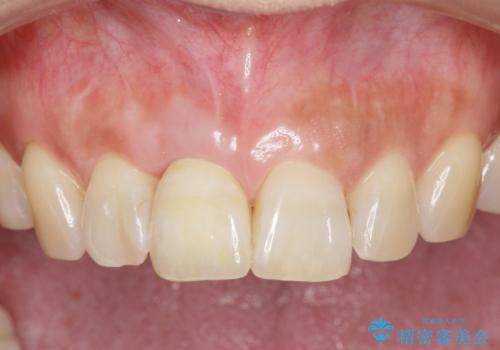

前歯のインプラントを審美的に仕上げるには、インプラント周囲に十分な骨の量と厚みのある歯肉、そして埋入位置の精密な位置付けが重要です。